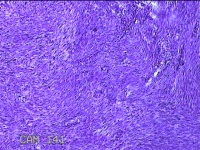

子宫肌瘤

性别

女

年龄

38岁

临床诊断

一般病史

发现子宫肌瘤复发7年余。

标本名称

大体所见

灰白粉红色结节样肿物8.5x5.5x4cm一个,表面糜烂,切面灰白色,编织状,质中。

富于细胞性平滑肌瘤

考虑富细胞平滑肌瘤。

组织处理和染色都不太理想。